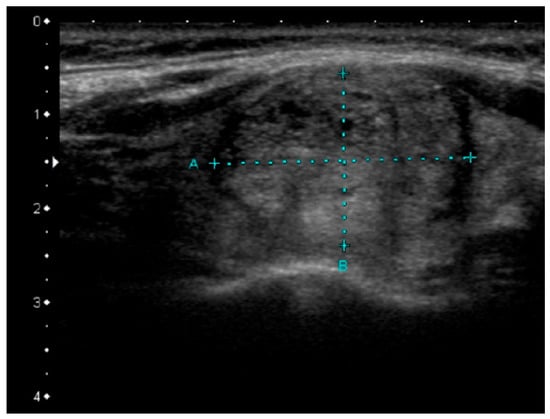

According to the 2017 WHO classification, two subtypes of FV PTC are distinguished: Invasive encapsulated FV PTC (i.e., the encapsulated FV with capsular or vascular invasion), and infiltrative FV, which is not encapsulated []. Invasive EFV PTC is associated with RAS mutation or PAX8-PPARγ and it constitutes 4% of all PTCs. Infiltrative FV accounts for 6% of all PTCs and is mainly caused by BRAF mutation, usually BRAFK601E, or, less often, RAS mutation [,,,]. BRAF mutations are therefore typical for the more aggressive infiltrative FV PTC while RAS mutations are often found in the less aggressive invasive EFV or the above-described NIFTP. US features of FV can suggest the tumor behavior and molecular landscape, as it can have typical PTC-like US patterns with hypoechoic lesions with irregular blurred margins and, sometimes, microcalcifications or rather follicular neoplasm-like patterns, without these markers of potential malignancy. Infiltrative FV is frequently a hypoechoic lesion, with spiculated/microlobulated margins. Microcalcifications can be present in about 20% of the cases. Nodules are often ovoid to round in shape, with a non-parallel orientation and mixed vascularization. The presence of microcalcifications is less common in the FV than in the classic variant of PTC (41.2% vs. 17.6%) [,]. Invasive encapsulated FV is typically a hypoechoic lesion with rather smooth margins and no calcifications. Nodule shape, orientation, and vascularity are similar to the infiltrative type of FV [,]. Similar observations concerning more benign US features of nodules harboring RAS mutations were presented by Rossi et al. [], who demonstrated that most of them were isoechoic. Nodules bearing RAS mutations were also larger than nodules with BRAFV600E mutations (>1 cm) []. Interestingly, de Napoli et al. [] observed microcalcifications and irregular margins in nodules with N-RAS mutation. US examination is a very good prognostic tool in examining follicular-patterned lesions with papillary nuclear features as the infiltrative FV PTC may be differentiated from the benign NIFTP on the basis of the US pattern. However, US-based discrimination between invasive EFVs and NIFTPs is rather impossible in clinical practice [,]. The presence of RAS mutations is usually associated with less aggressive forms of PTC and a more benign US image (Figure 4).

Figure 4.

Sonographic pattern of RAS-positive papillary thyroid carcinima, slightly hypoechoic, heterogeneous lesion with rather well-defined margins.